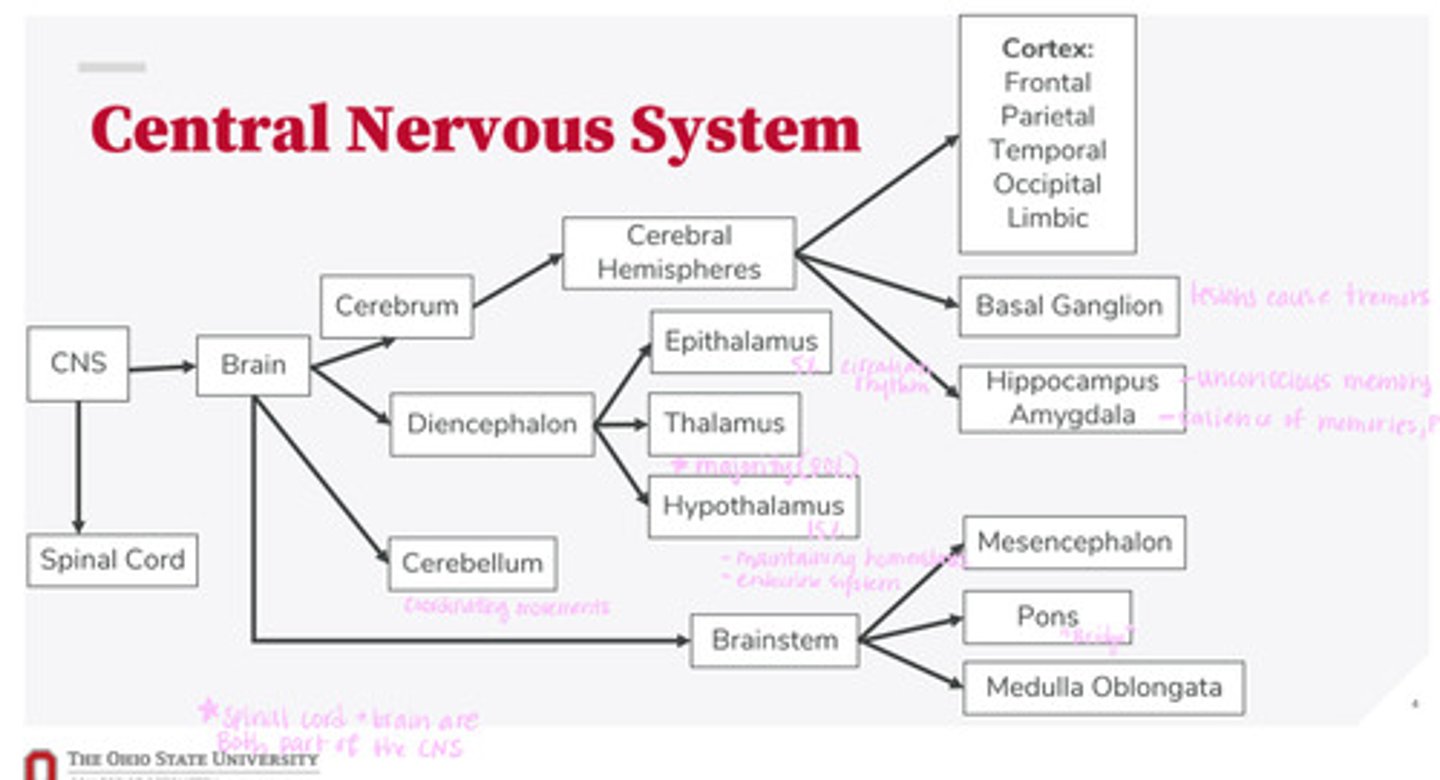

-brain

-spinal cord

What are the 2 divisions of the CNS?

-cerebrum

-diencephalon

-cerebellum

-brainstem

What are the 4 divisions of the brain?

-epithalamus

-thalamus

-hypothalamus

What are the 3 divisions of the diencephalon?

-mesencephalon

-pons

-medulla oblongata

What are the 3 divisions of the brainstem?

-cortex

-basal ganglion

-hippocampus

-amygdala

What are the divisions of the cerebral hemispheres?

-frontal lobe

-parietal lobe

-temporal lobe

-occipital lobe

-limbic system

What are the divisions of the cortex?

coordinating movements

What is the function of the cerebellum?

thalamus

A majority of signals from the diencephalon flow into where?

circadian rhythm

What is the function of the epithalamus?

-maintaining homeostasis

-endocrine system function

What is the function of the hypothalamus?

tremors

Lesions on the basal ganglion cause what?

hippocampus

What part of the brain is in control of unconscious memory?

amygdala

What part of the brain is in control of the salience of memories (PTSD)?

The bridge between the mesencephalon and the medulla oblongata

What is the function of the pons?